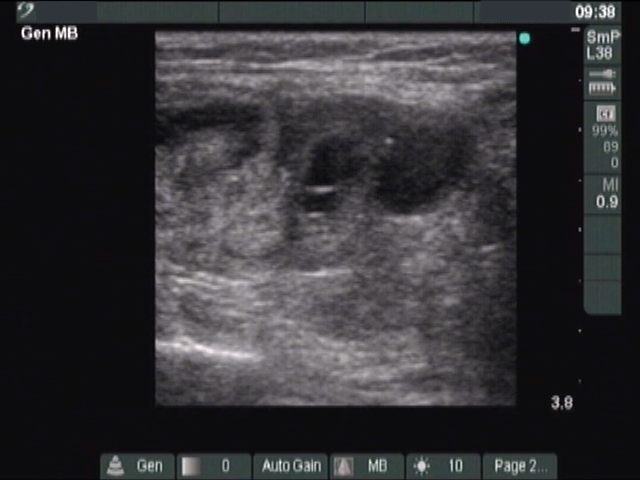

Benign nodular hyperplasia - Case 41. (ultrasonographic picture 6)

Left lobe, longitudinal scan. There is a hypoechogenic nodule in the lower pole.